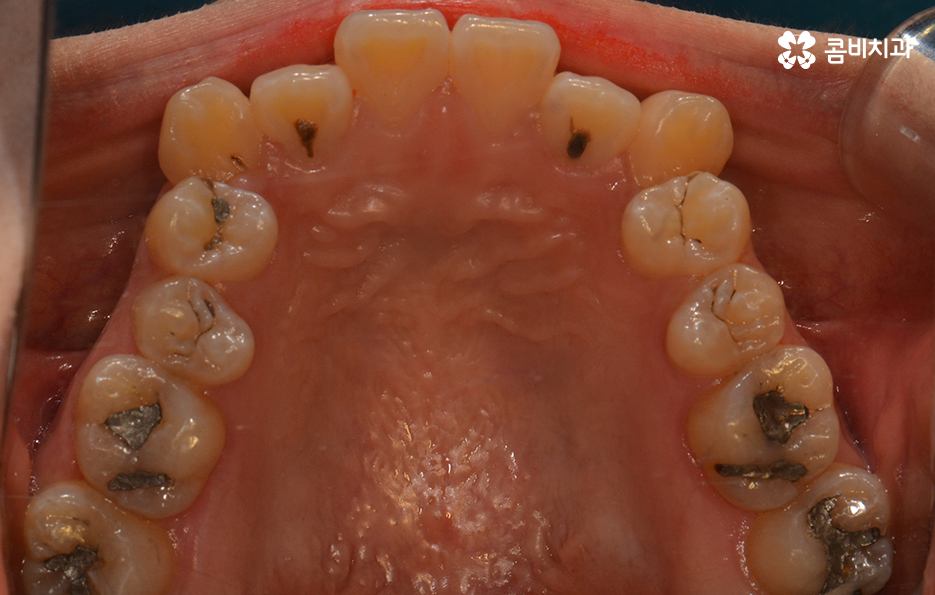

교정을 시작하기 전에 충치치료를 먼저 진행하였고 한 달 정도 소요됨

충치가 있다면 치료 후 교정이 시작되기 때문에

개개인의 상태에 따라 전체적인 치료 기간이 결정되게 됩니다.

추가로 사랑니의 경우에도 치료 기간에 영향을 줄 수 있는데요.

교정 전에 발치를 하는 경우, 중간에 하는 경우, 끝나고 하는 경우로

나눌 수 있으며, 정밀 검사를 통해 치료 계획을 세운 뒤

순차적으로 치료를 진행하게 됩니다.